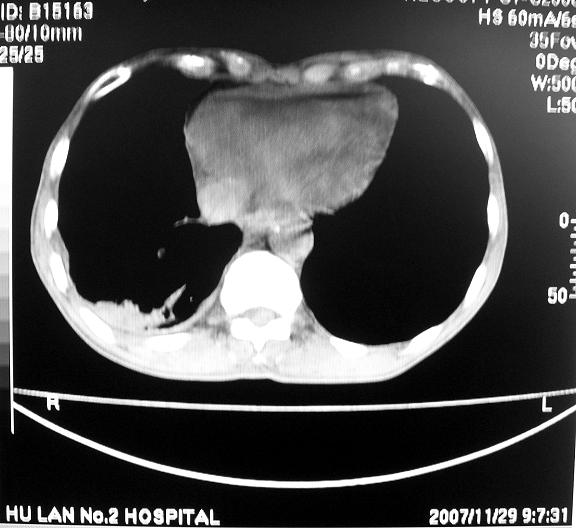

标题: CT10688:男63岁胸痛来诊

男63岁胸痛来诊

右肺病灶前缘不平整,略呈分叶状,其后方胸膜下脂线消失且似有向胸壁浸犯,左下肺球形灶内可见不规则空洞影,余双肺内可见多枚结节影,结合病史支持考虑肺癌肺内转移胸膜转移,便双肺后部病灶倒也是结核好发区域,建议穿刺活检

右下肺周围性肺ca并双肺及右侧胸膜转移。[emb6]

右下肺周围性肺ca并双肺及右侧胸膜转移。支持

右下肺周围性肺ca并双肺及右侧胸膜转移。

右下肺周围性肺ca并双肺及右侧胸膜转移。单看病变像炎性假瘤。

右下肺癌,双肺及胸膜转移

右下肺癌伴双肺及胸膜转移。